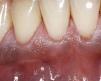

Pigmentación gingivalCriterios de diferenciación- •

Pigmentación negro-pardusca.

Origen racial.

También pigmentaciones en otras zonas de la mucosa.

La anamnesis no aporta datos relevantes.

Posible presencia en personas de piel más intensamen-te pigmentada.

TratamientoNo requiere tratamiento.